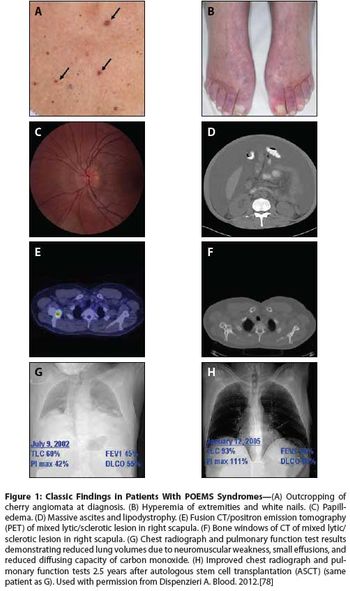

POEMS syndrome is a rare paraneoplastic syndrome that is caused by an underlying plasma cell disorder. Its main features include polyradiculoneuropathy, organomegaly, endocrinopathy, monoclonal plasma cell disorder, and skin changes.